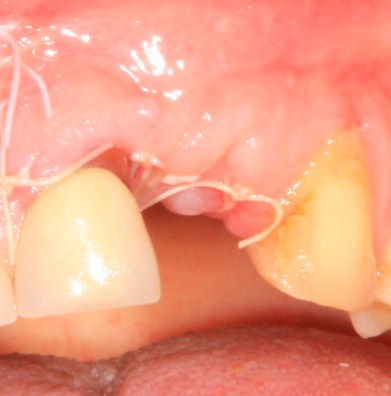

После чего я это самое контурирование и делаю:

а когда десна более-менее заживает:

он меняет временные коронки на более естественные. С этого момента мы уже можем оценить первые результаты нашей работы: